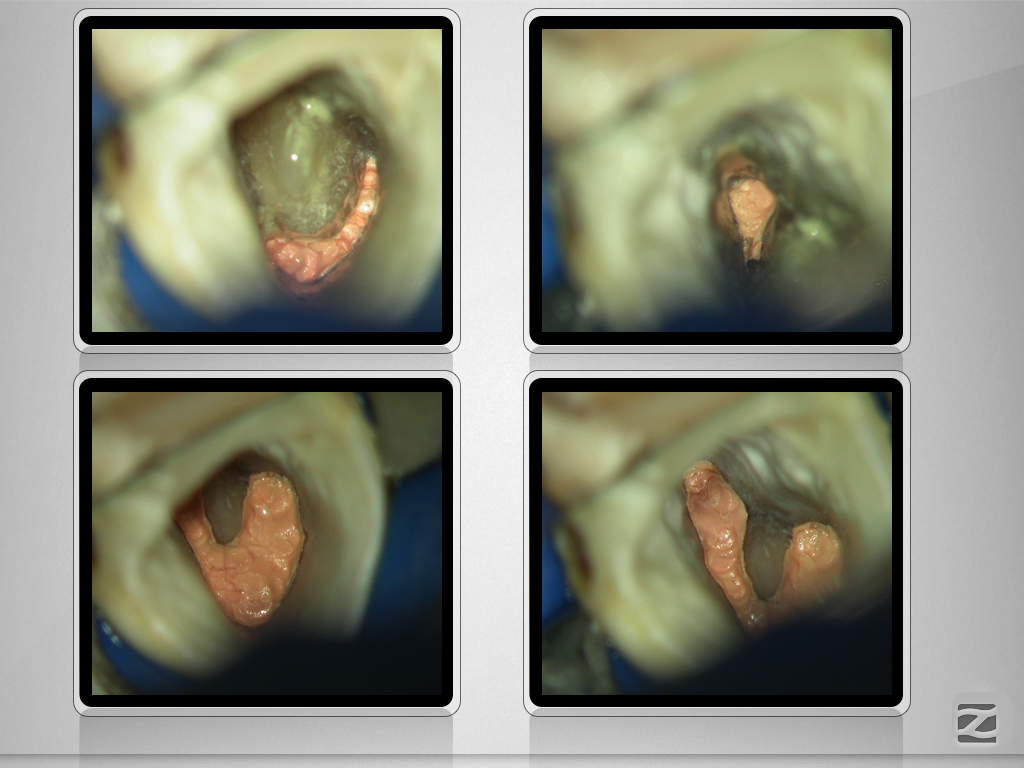

36D.008

1024 × 768

Doppeltes C